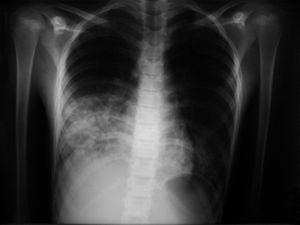

Se trata de un niño de 12 años y 38 kg de peso, ingresado para realización de endoscopia digestiva con cápsula en el contexto del estudio de un sangrado digestivo no filiado. Como preparación del procedimiento a realizar se inició administración de solución evacuante de PEG por SNG. Tras haber administrado un litro de la solución en un espacio de 60 min presentó vómitos, sensación de plenitud, dolor costal derecho y dificultad respiratoria con hipoxia (saturación de oxígeno al 80 %). En la radiografía de tórax se observó condensación alveolointersticial granular bibasal (fig. 1), sin que se encontraran alteraciones significativas en la bioquímica plasmática ni en el hemograma, siendo la proteína C reactiva (PCR) de 0,5 mg/dl. Se procedió a traslado a UCIP donde se instauró tratamiento con oxígeno suplementario, antibioterapia (clindamicina y ceftacidima intravenosas) junto con metilprednisolona, consiguiendo remisión de la clínica y adecuada oxigenación. Posteriormente, presentó picos febriles y elevación de la PCR hasta 25 mg/dl. La evolución fue favorable, cediendo la fiebre y pudiendo retirar el aporte de oxígeno suplementario tras 72 h, lo que permitió su paso a planta de hospitalización. Al alta, tras 2 semanas de ingreso hospitalario la resolución tanto clínica como radiológica fue completa.

Figura 1. Radiografía de tórax: neumonía aspirativa bibasal.